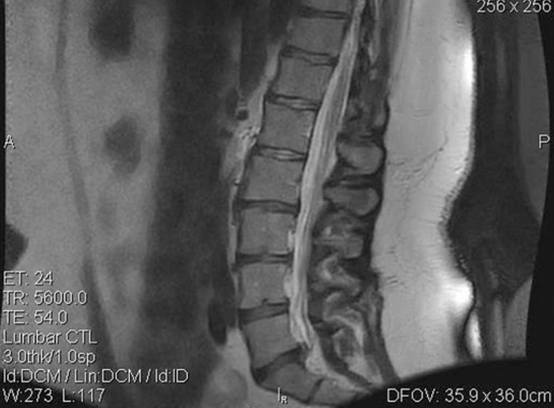

A 35-year-old female presented at an outpatient clinic in July 2006 complaining of LBP. The back pain was associated with numbness and recurrent right leg pain. The treating physician noted that the patient’s condition had been chronic since December 2004. These symptoms affected her ability to lift clients – a required part of her occupational duties – and were aggravated by sitting and prolonged standing. The patient weighed 291lb and was 5’ 8” tall. Her history was significant, with two motor vehicle accidents (in 1994 and 2002). Magnetic resonance imaging (MRI) of the lumbar spine performed on 19 July 2006 revealed a mild to moderate disc protrusion at L5/S1, eccentric to the right, impinging on the right S1 nerve root (see Figure 1). Mild degenerative changes with minimal bulging were also noted at L2/L3 and L3/L4. Upon initial examination, the patient presented limited lumbar range of motion (ROM), with pain in all planes, positive nerve root tension tests and decreased sensory and motor function of the right lower extremity.

At initial treatment, the patient reported pain at 7 on a 0–10 scale; at the end of the treatment protocol she reported pain at 1. A reduction in the duration of pain was noted as well: pain initially occurred 75% of the time, but decreased to 10% of the time at completion of treatment. At final evaluation, the examiner noted an improvement in lumbar ROM tests: flexion increased from 42 to 58º, extension increased from 12 to 26º, left lateral flexion increased from 14 to 25º and right lateral flexion increased from 12 to 24º. Orthopaedic and neurological findings were noted as normal. Limited follow-up MRI of the lumbar spine performed on 22 September 2006 revealed a decrease in the excursion of the disc at L5/S1 on T2-weighted sagittal images (see Figure 2).

Figure 1: Pre-treatment Magnetic Resonance Image

Figure 2: Pre-treatment Magnetic Resonance Image